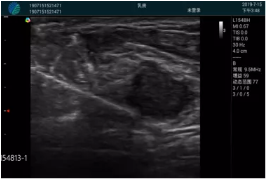

病例二:

腺體內(nèi)部清晰顯示一低回聲塊影,形態(tài)不規(guī)則,邊界模糊,邊緣呈毛刺狀,內(nèi)部見砂礫樣鈣化

M20引導(dǎo)下穿刺活檢術(shù)

M20引導(dǎo)下平面內(nèi)穿刺取出的腫塊組織